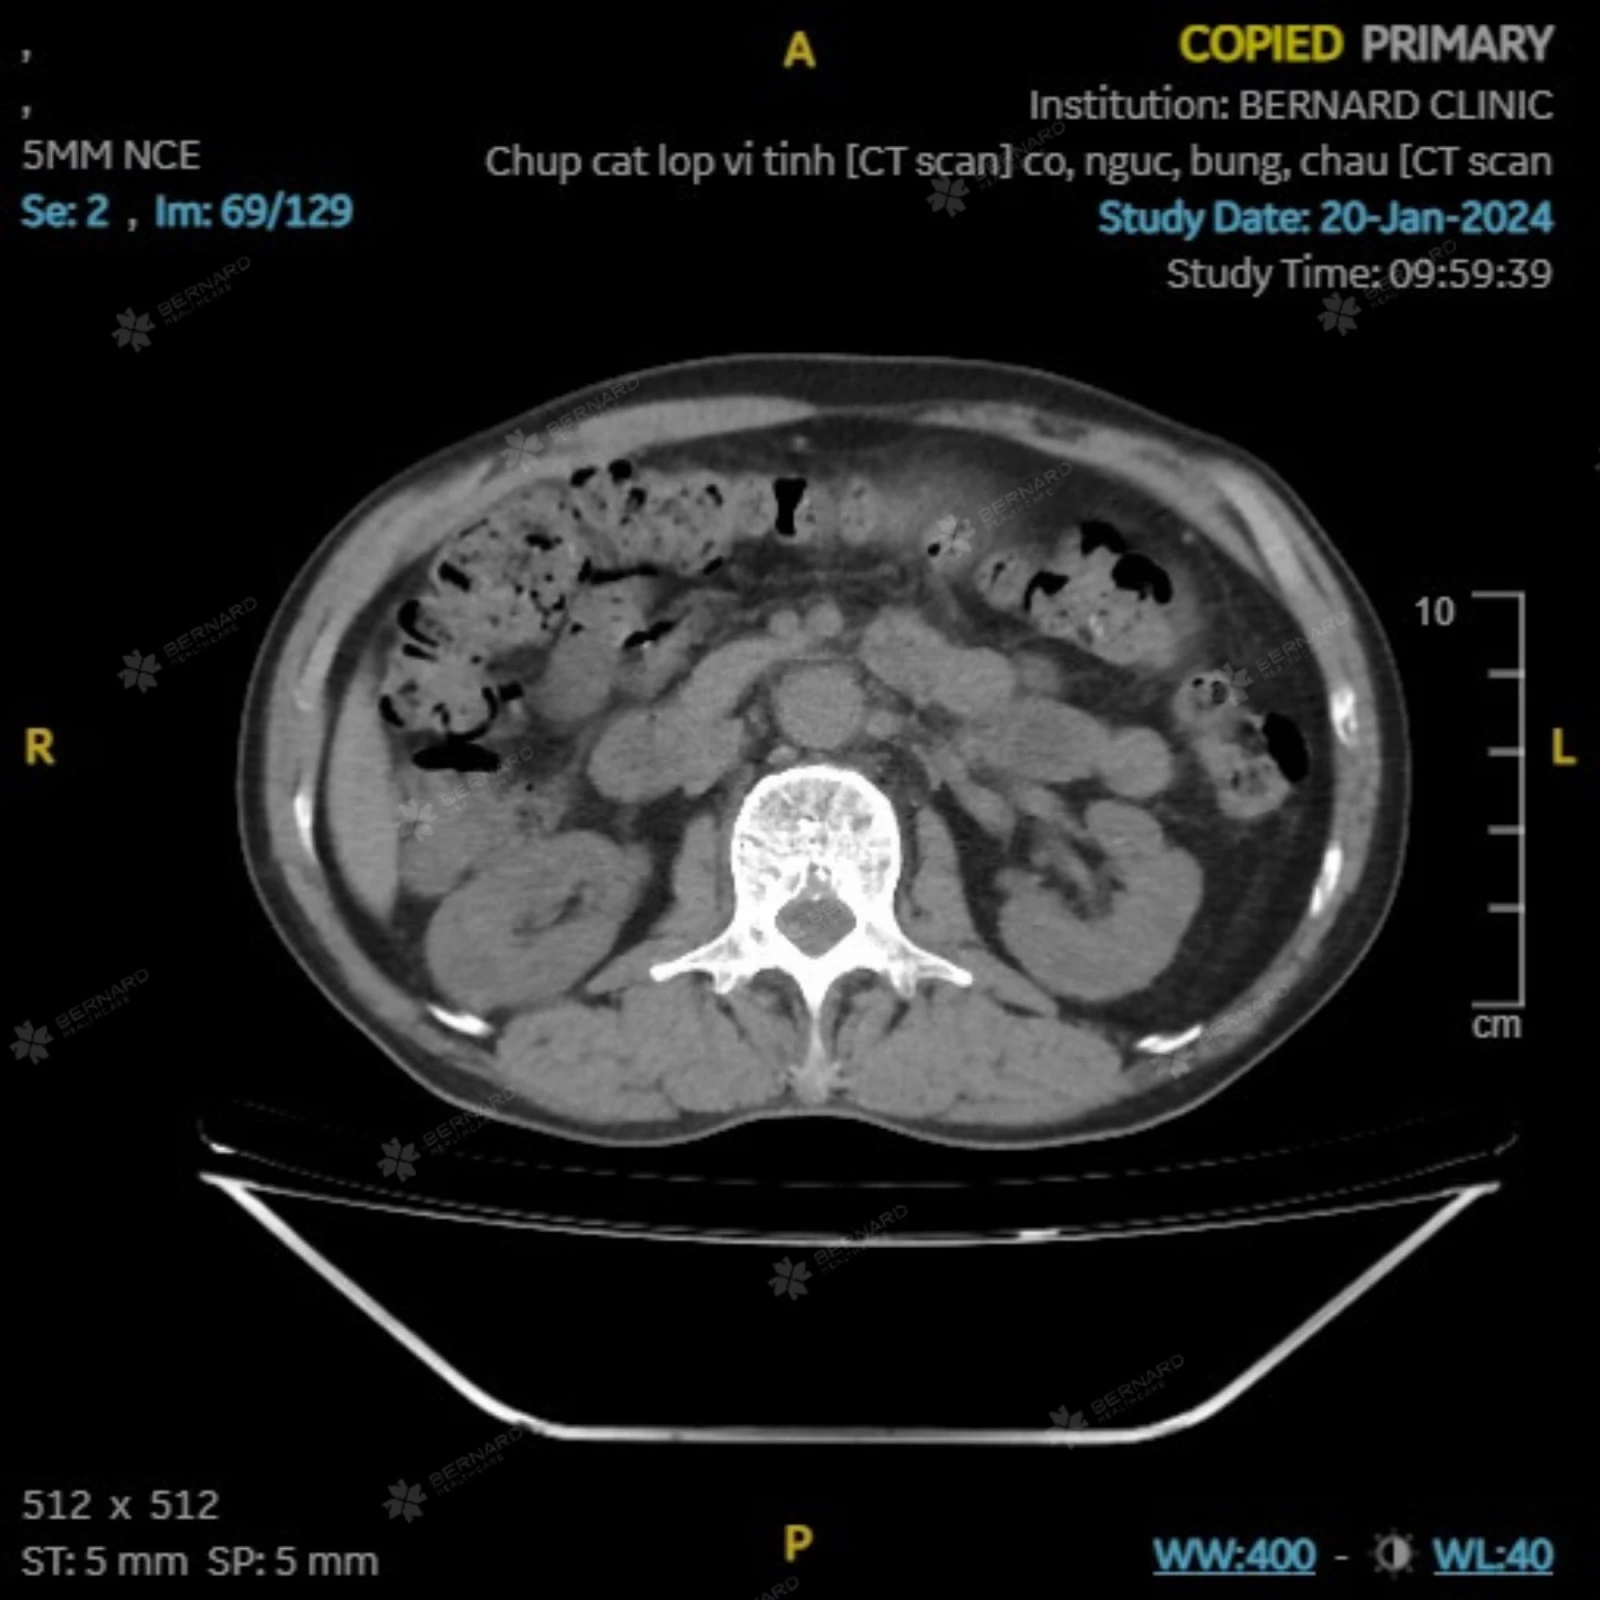

Bernard Healthcare từng ghi nhận trường hợp nam bệnh nhân 58 tuổi, có tiền sử hút thuốc lá nhiều năm (5 - 6 điếu mỗi ngày kéo dài hơn 15 năm (tương đương khoảng 4 gói-năm) và sử dụng rượu bia với tần suất cao (khoảng 8 - 10 lon mỗi lần, 3 lần mỗi tuần), đến khám sức khỏe tổng quát trong tình trạng không có triệu chứng hô hấp rõ ràng.

Dựa trên đánh giá nguy cơ, bác sĩ chỉ định thực hiện CT Scan phổi liều thấp. Kết quả cho thấy tổn thương choán chỗ lớn tại thùy dưới phổi phải, với các đặc điểm hình ảnh học gợi ý u phổi cần theo dõi ung thư. Trường hợp này cho thấy, phổi có thể “chịu đựng” tổn thương trong thời gian dài mà không biểu hiện triệu chứng đặc hiệu.